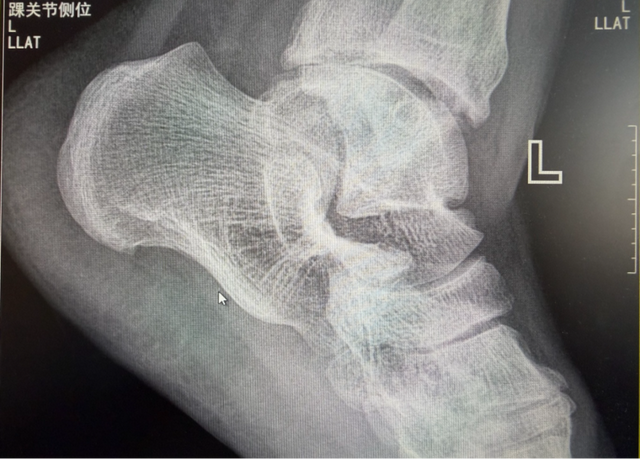

手术前后影像对比

在几乎失去希望之际,张叔在家人的鼓励下来到我院骨科就诊。经过详细的问诊与检查,医生发现其脚踝情况远比想象中更为复杂。影像检查结果清晰地揭示出关节内部“千疮百孔”的真相:

o 软骨严重磨损(就像轮胎磨没了纹路)

o 骨头里有很多“小空洞”(骨髓水肿)

o 关节积水、韧带损伤